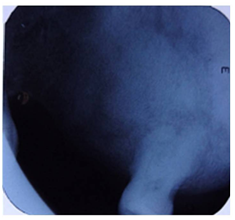

The investigations advised included the complete blood picture, intraoral periapical radiograph, maxillary occlusal view, panoramic radiograph and CBCT. Periapical radiograph and maxillary left lateral topographical occlusal view a revealed diffuse patchy radiolucency in region of 26, 27 along with multiple flecks of fine calcifications and hypercementosis was seen with respect to 28 (Figure 2) (Figure 3). Panoramic view revealed radiopacity extending from 24 to tuberosity and encroaching onto the maxillary sinus (Figure 4). To make out the exact extent of the lesion CBCT imaging was planned. CBCT sections showed mixed radiopaque radiolucent (predominately radiopaque) lesion, with well defined borders, extending from 24 till tuberosity region (Figure 5) measuring anteroposteriorly 4cm ,superoinferiorly 5cm ,and mesiodistally around 2.5cm in dimension. The pterygoid plates though intact, the lesion however did superimpose on the maxillary sinus. No secondary reaction in the sinus could be appreciated. With a clearer picture on the extent of the lesion, we took the next step towards the management.

Figure 4 Panoramic view revealed radiopacity extending from 24 to tuberosity and encroaching onto the maxillary sinus.